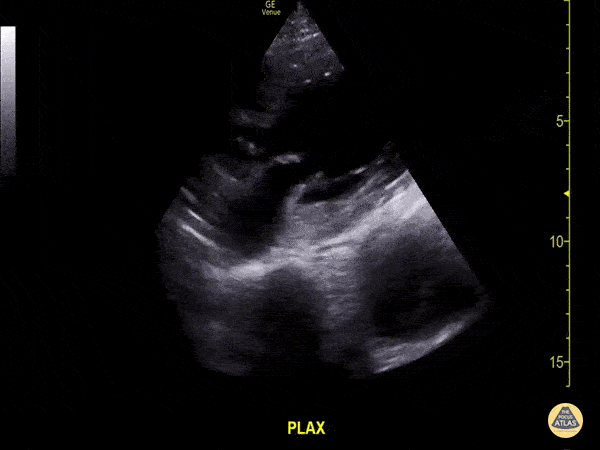

Aorta - Thoracic Aorta Aneurysm with Intramural Thrombus

Don’t be distracted by the abnormal cardiac function in this clip, notice deep to the pericardium a thoracic aorta aneurysm is seen with moderate amount of intramural thrombus. Image courtesy of Aventura Ultrasound; Their original Twitter posting can be found here.